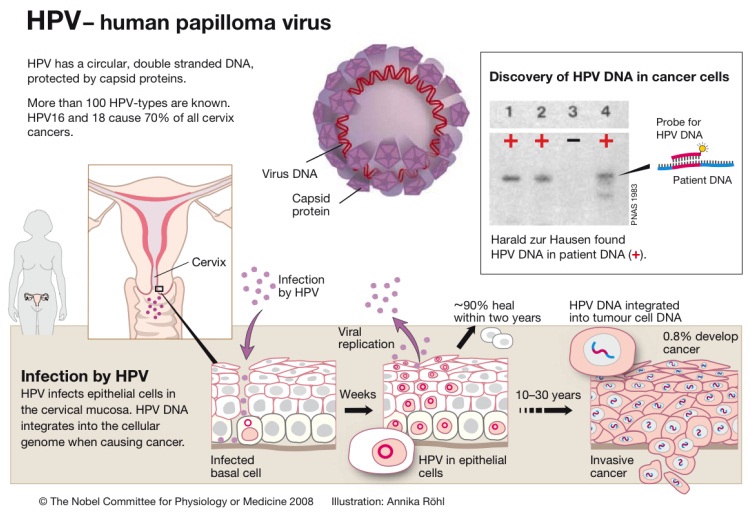

Human Papilloma Virus

HPV – group of 150 related viruses, resulting in warts (papillomas)

HPV – group of 150 related viruses, resulting in warts (papillomas)

HPV is the most common sexually transmitted infection. HPV is a viral infection that can be spread from one person to another person through anal, vaginal, or oral sex, or through other close skin-to-skin touching during sexual activity. If you are sexually active you can get HPV, and nearly all sexually active people get infected with HPV at some point in their lives. HPV16 and HPV18 cause 70% of all cervical cancers.